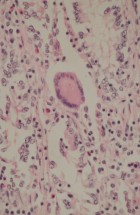

Делатност Одељења обухвата истраживачки и специјалистичко – стручни рад. Одељење се бави клиничком, патоанатомском, патохистолошком, имунохистохемијском и молекуларном дијагностиком обољења домаћих и дивљих животиња, као и патологијом репродукције. Рад на одељењу је организован кроз теренске и лабораторијске активности.

- Патохистолошка, цитолошка, имунохистохемијска и молекуларна дијагностика;